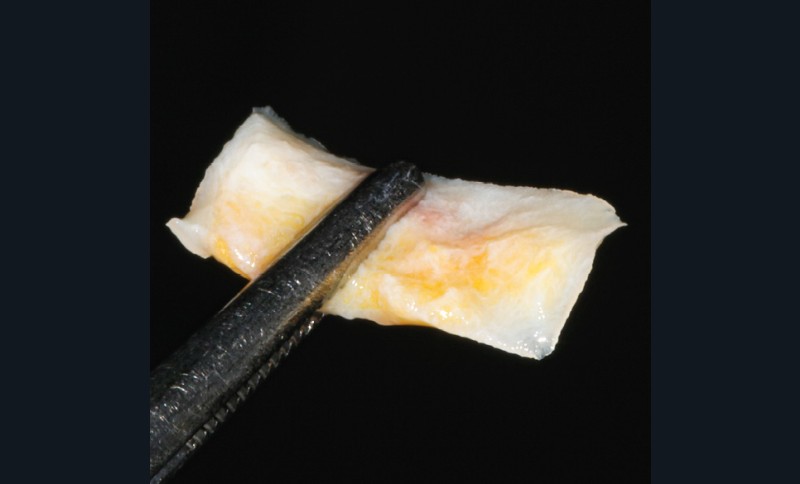

– Le laser Er-YAG, utilisé pour le nettoyage, est un laser avec un milieu actif composé d’yttrium, d’aluminium et de grenat dopé à l’erbium. Avec une longueur d’onde de 2 940 nm situé dans l’infrarouge, le laser Er-YAG est un laser à haute énergie, dont la lumière est absorbée dans l’eau et dans l’hydroxyapatite et qui ne pénètre pas profondément. Ceci permet de couper des tissus mous et des tissus durs, mais également de désorganiser le biofilm bactérie.